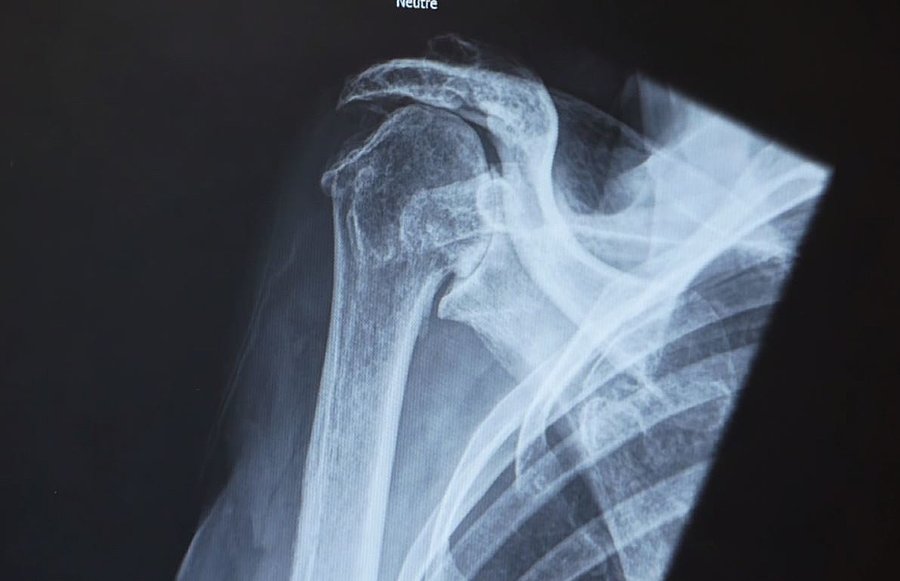

Notre équipe de chirurgiens orthopédistes, de chirurgien plastique reconstructrice, de physiothérapeutes est spécialement formée pour traiter une gamme complète de conditions liées à l'épaule, au coude et au membre supérieur. Que ce soit pour des blessures sportives, des troubles dégénératifs ou des traumatismes, nous offrons des solutions adaptées à chaque individu.